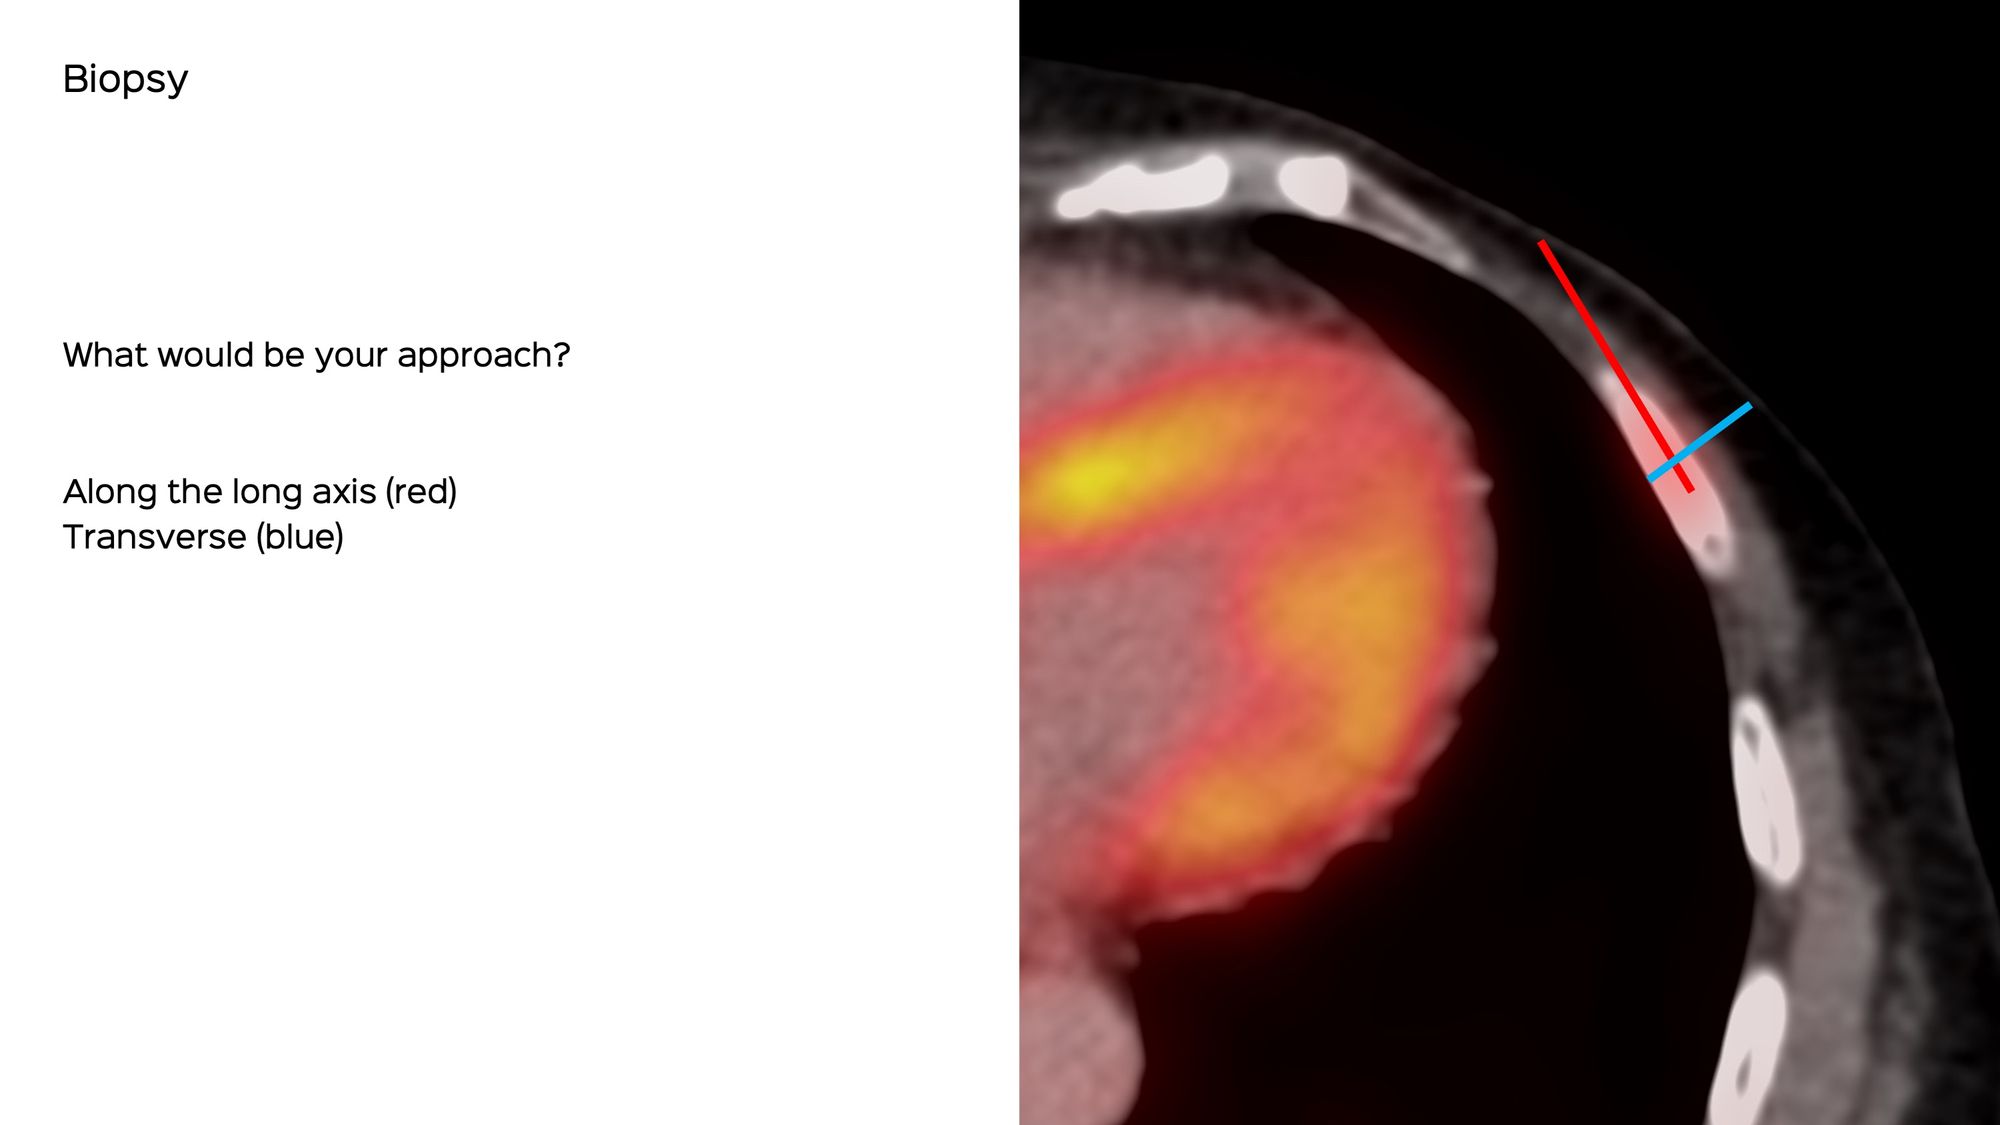

A 70-years old treated in the past for carcinoma breast was found to have a new, sclerotic left 5th rib lesion on PET, confirmed on MRI. She was refused a biopsy because of the risk of lung injury.

She came for an opinion and we agreed to do a biopsy.